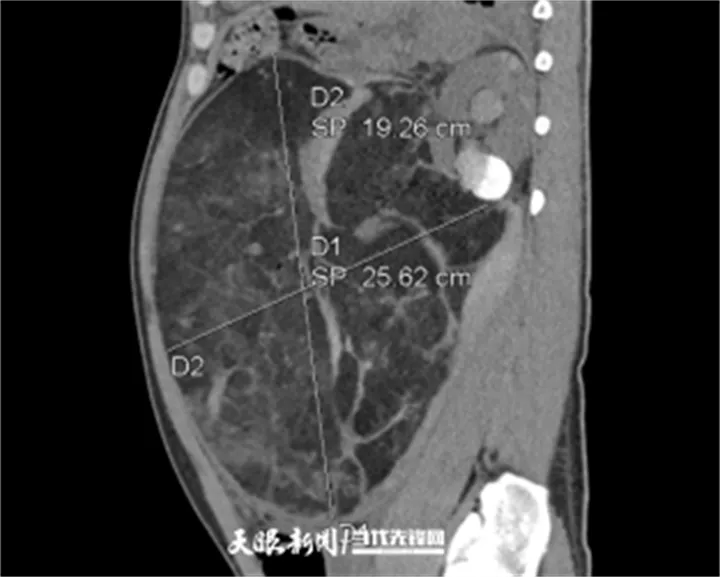

据了解,长期疏于体检的张先生(化名)因突发剧烈腹痛、头晕心慌急诊入院。当时他已出现血压下降、心率加快等休克前兆。急诊CT显示:左肾巨大错构瘤破裂出血,肿瘤体积达27cm×25cm,严重压迫周围脏器,活动性出血持续不止。

近日,因长期疏于体检,张先生突发剧烈腹痛并伴头晕心慌,被紧急送至贵州医科大学附属医院。急诊CT检查结果令人震惊:其左肾内长有一个体积达27cm×25cm的巨大错构瘤,并且已经破裂出血。

急诊CT显示,患者左肾巨大错构瘤已破裂出血。

33 岁的张先生(化名)突发剧烈腹痛伴头晕心慌,来到贵医附院看诊。医生了解到,张先生长期疏于体检,医院急诊CT 检查确诊为左肾巨大错构瘤破裂出血—— 肿瘤体积竟达 27cm×25cm,相当于一个篮球大小!